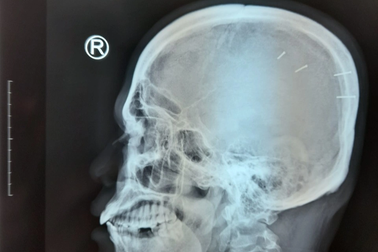

Bé 3 tuổi bị ghim 9 cây đinh trong đầu: Phẫn nộ và rụng rời xót xa!Cộng đồng lại dậy sóng khi mới đây một em bé 3 tuổi nhập viện trong tình trạng nguy kịch, qua chụp chiếu kiểm tra nghi rằng bé bị ghim 9 cây đinh vào đầu, vết thương bên ngoài đã liền da.